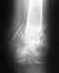

Ситуация здесь непростая. Стандартное эндопротезирование тут не годится, нужен ревизионный или онкологический протез, да и риск инфекции очень высок. Эндопротезирование коленного сустава делают и в Курганском РНЦ, где Вы уже были. Обсуждали там этот вариант?

Можно обсуждать артродез (замыкание) коленного сустава с остесинтезом длинным внутрикостным стержнем бедро-голень. Сравнительных снмков нет, еще и про укорочение то есть нет информации.

Спасибо что ответили....укорочение после наложения аппарата илизарова есть 5 см...в кургане мне и пытались замкнуть сустав, но консолидации не добились...а вскрывать они боятся...проблема обсуждалась...но я готова пойти на риск пусть лучше заражение и тд чем мучится болями столько лет...возможно у Вас есть информация какие клиники в порядке может эксперимента возьмутся что либо сделать..снимок с отправляла Вам с тех пор по заключению наших врачей при прохождении МСЭК ставят диагноз не сросшийся перелом..может что то посоветуете куда можно обратится.Заранее благодарна.